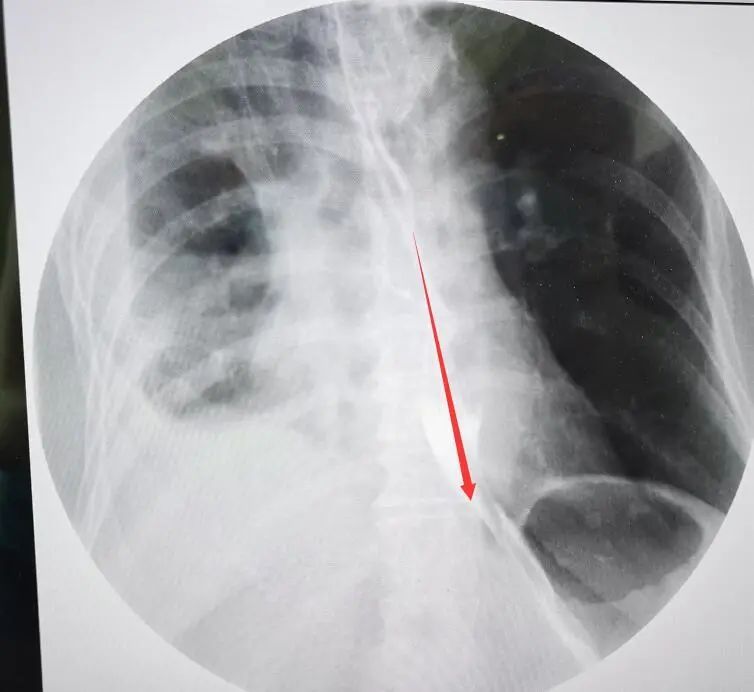

復(fù)查食管造影,顯示無(wú)造影劑漏出。之后通過(guò)胃鏡明確破裂口愈合。